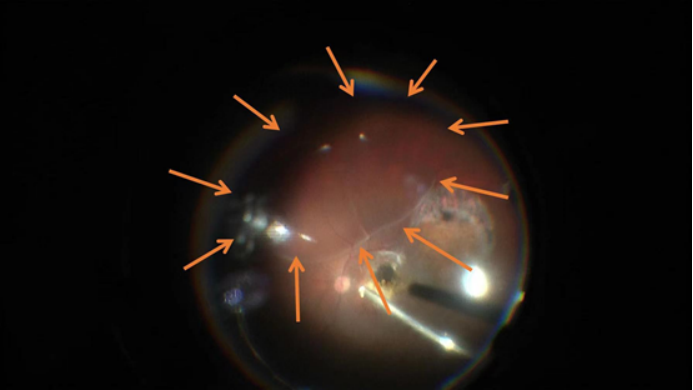

視網(wǎng)膜下注射KH631成功后的2個水泡

? ? ?當天下午在給藥后7小時查看受試者,眼部及全身情況良好,玻璃體腔內(nèi)氣體填充,視網(wǎng)膜下存在水泡(KH631藥液)。術后第一天早晨,張主任再次查看受試者發(fā)現(xiàn)其視網(wǎng)膜下藥物液泡已經(jīng)完全吸收,視網(wǎng)膜完全恢復平伏。目前術后1周,受試者眼部及全身情況均良好,視力恢復到注藥前,OCT顯示黃斑情況穩(wěn)定,準予出院。